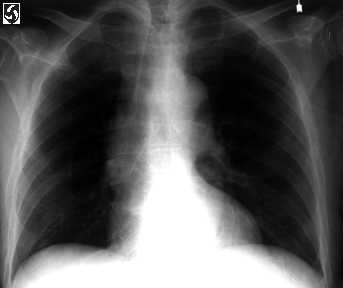

Derecho radiograph del pecho

Un anteroposterior el pecho derecho radiograph demuestra pulmones claros sin la evidencia de una parenchymal o pleural anormalidad.

En la mayor�a de los pacientes, pecho radiograph los hallazgos en pulmonares embolus (PE) son nonspecific o parejos unremarkable. El pecho radiograph puede mostrar una pleural efusi�n, atelectasis, and/or consolidaci�n pulmonar. Menos hallazgos comunes son la hipertensi�n pulmonar, congestive el fallo de coraz�n, Westermark's firma (ampliaci�n de las embarcaciones centrales con fragmentarias o lobulares oligemia), y Hampton's encorva (una cu�a - la formada opacidad que linda la pleura debido a pulmonar infarction). El pecho de este paciente radiograph era normal.